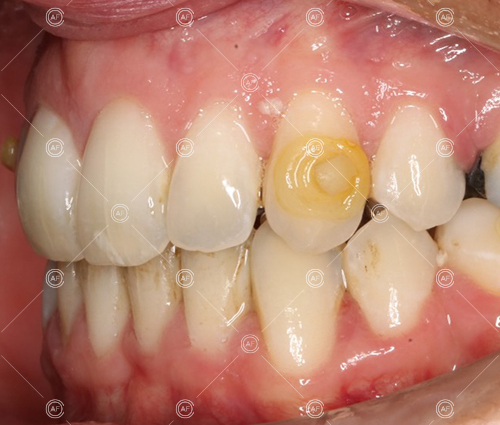

This patient (MH) began her active orthodontic treatment in October 2019 at almost 13 years old. She was unhappy with the appearance of her upper and lower teeth, and especially concerned about the unsightly nature of the high and buccally positioned upper left canine.

Buccal segments were essentially class 1 on the right hand side and a full unit class 2 on the left. This is due to buccal exclusion of the upper left 3 and mesial drift of the upper buccal segment.